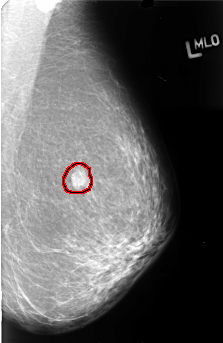

B_3410_1.LEFT_MLO

FILE: B_3410_1.LEFT_MLO.OVERLAY

TOTAL_ABNORMALITIES 1

ABNORMALITY 1

LESION_TYPE MASS SHAPE OVAL MARGINS OBSCURED

ASSESSMENT 3

SUBTLETY 5

PATHOLOGY MALIGNANT

TOTAL_OUTLINES 1

BOUNDARY